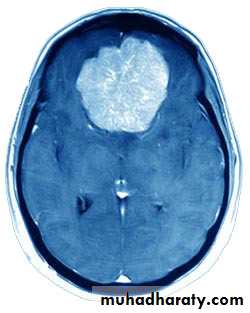

MeningiomaPre contrast CT

Neuro surgery

MeningiomaPost contrast CT